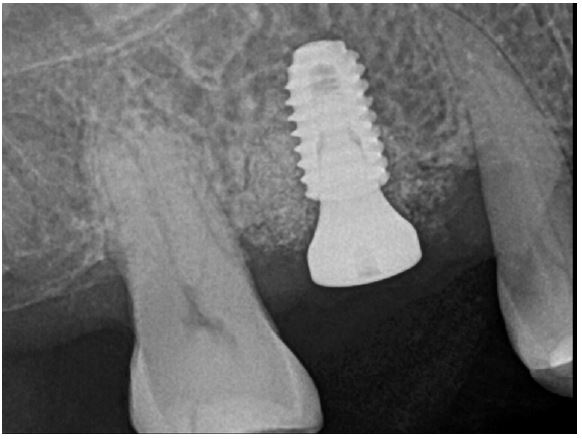

Four months after the first surgery for the implant, reopening for the second surgery, the site demonstrated that the fixture was surrounded by new bone, and the ISQ value was 68 (Fig. 14A, 14B). Subsequently, a 6.0 mm diameter, 7 mm length healing abutment was placed (Fig. 15).

A 2-year follow-up CBCT view revealed that the condition was maintained without any complications for 21 months after prosthesis placement (Fig. 16A, 16B).